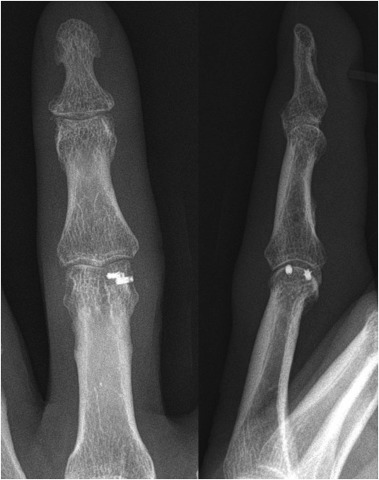

Fig. 4

Fig. 4.

Post-operative anteroposterior and lateral plain radiographs demonstrating two micro-suture anchors on the head of the proximal phalanx.